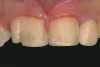

A 9-year-old girl, referred to a prosthodontic office by her pediatric dentist, presented with her mother’s chief complaint: “The kids are teasing her about her big front tooth.” Findings from radiographic and clinical examinations revealed fused maxillary central-peg lateral incisors, teeth Nos. 7 and 8, and a congenitally missing lateral incisor, tooth No. 10 (Figure 1 through Figure 3). An implant was selected as the ideal treatment to replace tooth No. 10 when somatic growth was complete. A diagnostic wax-up was fabricated to determine if the fused tooth could be made to resemble two teeth, using pink composite to give the illusion of an interproximal papilla. The patient was referred for an orthodontic consultation to plan for closure of the diastema between teeth Nos. 8 and 9 and achievement of proper alignment for implant No. 10. The patient was also referred to a periodontist for pretreatment assessment of the tooth No. 10 site. An endodontist was consulted should exposure of the large pulp occur during tooth preparation.

Fig 1 and Fig 2. Pretreatment photographs. Patient at 9 years of age on presentation.